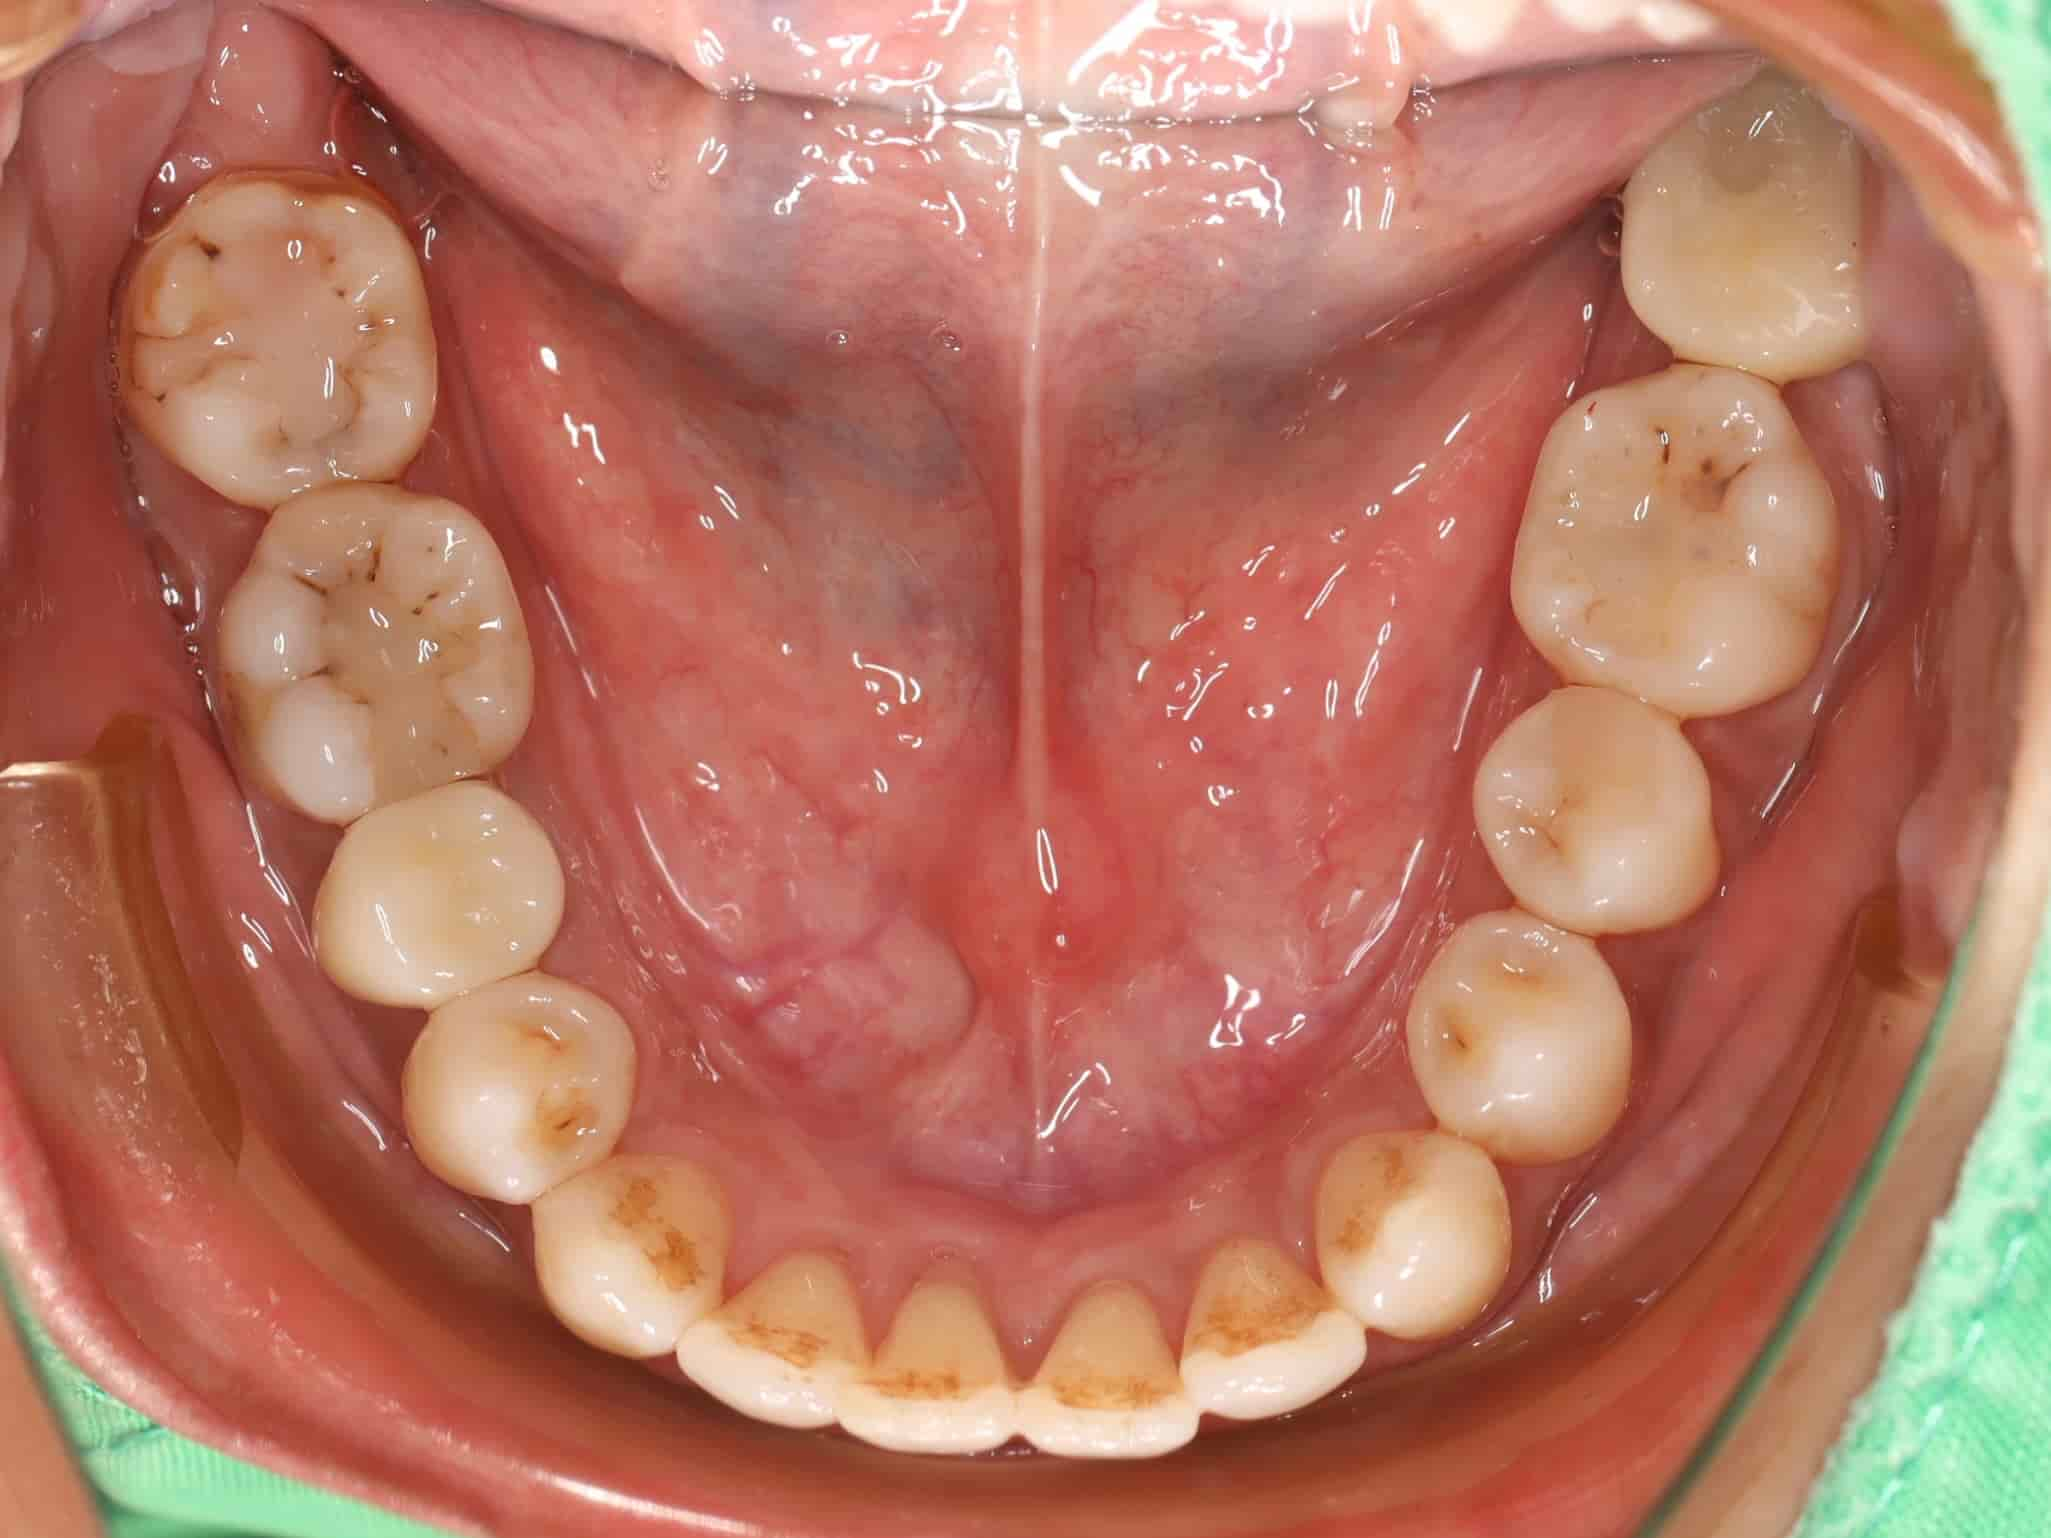

古小姐第一次來到診間時,主要是希望能做全口的詳細評估與檢查,因為她進食較黏稠的食物,牙齒容易感到疼痛,刷牙的時候容易出血,更令她困擾的問題是,她以前因為蛀牙拔掉牙齒,但沒有進行後續處理,左下方有缺牙的情況,除了導致牙齒開始出現縫隙,長期習慣用右邊進食,也讓她兩邊咬合都不太舒服。

左邊缺牙問題 - 長期缺牙導致排列與咬合問題

等到牙齦狀況穩定後,開始約一年的隱適美療程。矯正過程不只是要關閉牙縫,更重要的是要調整牙齒的角度和位置。由於缺牙時間過久,導致上方對咬牙失去抗衡,隨時間逐漸往下掉,因此也需要藉由矯正的力量把它們推回正確的位置。

矯正的中後期,當缺牙處的空間穩定後,我們就開始評估植牙的可能性。後續就進行植牙手術並做補骨補肉處理,為新牙齒打造穩固的地基。